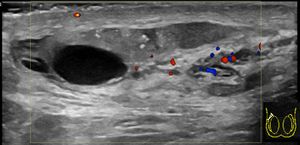

진단은 일반적으로 증상을 기반으로 한다.[1] 유사한 증상을 유발할 수 있는 질환으로는 고환 염전, 서혜부 탈장, 고환암 등이 있다.[1] 진단이 불분명한 경우 도플러 초음파 검사가 유용할 수 있다.[1]

정교한 의학 영상 기술이 개발되기 전에는 외과적 탐사가 표준 치료법이었다. 오늘날에는 도플러 초음파 검사가 일반적인 검사이다. 이는 혈류 영역을 보여주고 부고환염과 염전을 명확하게 구별할 수 있다. 그러나 염전 및 고환 통증의 다른 원인은 촉진만으로도 종종 확인할 수 있으므로, 일부 연구에서는 초음파의 유일한 실질적인 이점은 고환암이 없음을 환자에게 확신시키는 것이라고 제안했다.[10] 핵의학적 고환 혈류 검사는 드물게 사용된다.

정교한 의학 영상 기술이 개발되기 전에는 외과적 탐사가 표준 치료법이었다. 오늘날에는 도플러 초음파 검사가 일반적인 검사이다.[10] 이는 혈류 영역을 보여주고 부고환염과 염전을 명확하게 구별할 수 있다. 그러나 염전 및 고환 통증의 다른 원인은 촉진만으로도 종종 확인할 수 있으므로, 일부 연구에서는 초음파의 유일한 실질적인 이점은 고환암이 없음을 환자에게 확신시키는 것이라고 제안했다.[10] 핵의학적 고환 혈류 검사는 드물게 사용된다.